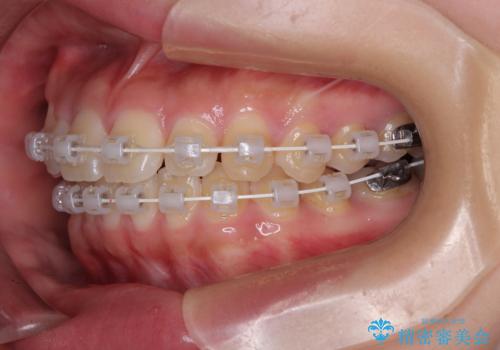

- 審美装置

- 8ヶ月

- 上下前歯のデコボコを気にして来院された患者様です。

ワイヤー矯正でもマウスピース矯正でも可能でしたが、短期間で、自身の手を煩わせることなく治療を行いたいとのことで、ワイヤー装置にて矯正治療を行うこととしました。

僅か8ヶ月という短期間で、綺麗な歯列に仕上がりました。